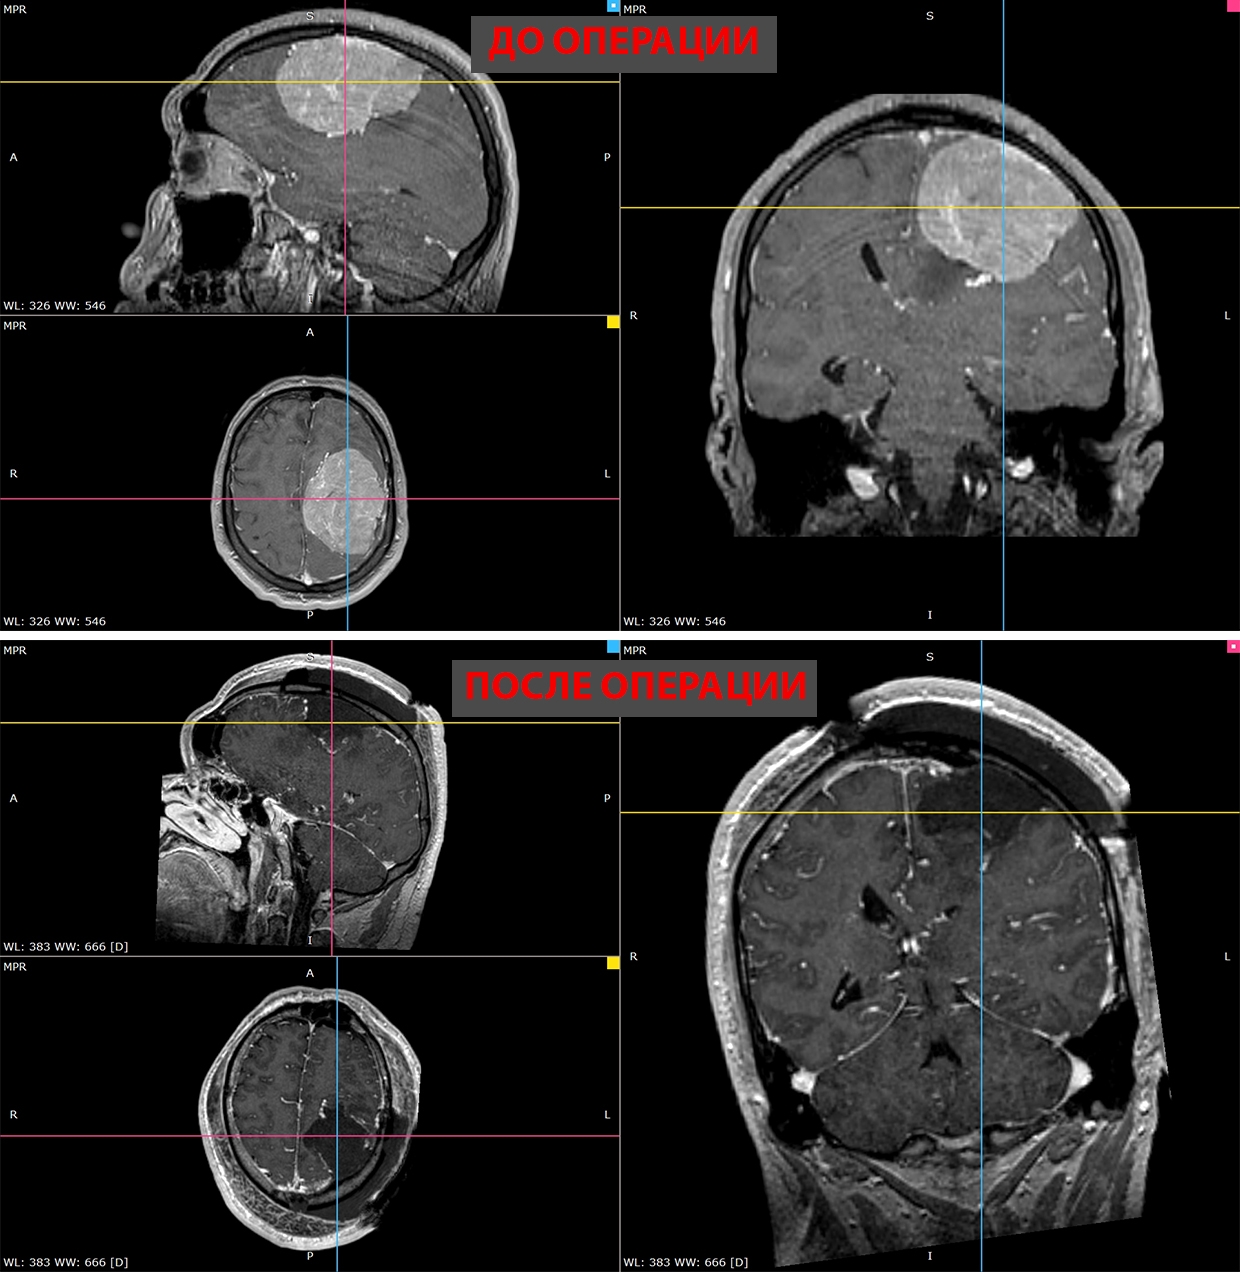

В Новосибирске врачи удалили 35-летнему пациенту гигантскую опухоль головного мозга. Об этом сообщает пресс-служба НМИЦ имени Мешалкина Минздрава России.

В ноябре прошлого года у мужчины появилась слабость в правой руке и затруднения речи — МРТ выявила у него менингиому диаметром более восьми сантиметров в левом полушарии мозга. К концу года рука практически перестала работать, ходьба давалась пациенту с трудом.

Пятичасовая операция прошла успешно. Опухоль удалили полностью. Уже на следующий день появились движения в руке, через две недели пациент снова стал сам ходить. У него восстановились речь и движения, приступы исчезли.